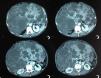

A 70-year-old man could provide no personal or family medical history. He sought medical attention for abdominal distension and symmetrical non-gravitational lower limb edema that he had presented with for many years, accompanied with anorexia and early satiety. Physical examination revealed protein-caloric malnutrition and jaundice of the skin and mucosae. There was a large, hard, non-painful, polylobular abdominal tumor in the right hypochondrium. The lower limbs presented with edema extending to the upper thigh that was nonpainful, with no fluxive signs. Abdominal computed tomography (CT) scan identified heterogeneous hepatomegaly and plain-looking multiple cysts substituting almost the entire parenchyma. One of them was compressing the vena cava and another had a hemorrhagic content. There were no elements of portal hypertension. The kidneys were normal. Medical treatment with nutritional support and diuretics was given. Liver transplantation or partial hepatic resection were not considered due to the patient's poor general status. A CT-guided transparietal puncture was carried out on the 2 largest cysts, draining a total of 600 cc, and alcohol instillation was done. The patient progressed well, with reduced edema and improved appetite and nutritional status (Figs. 1 and 2).